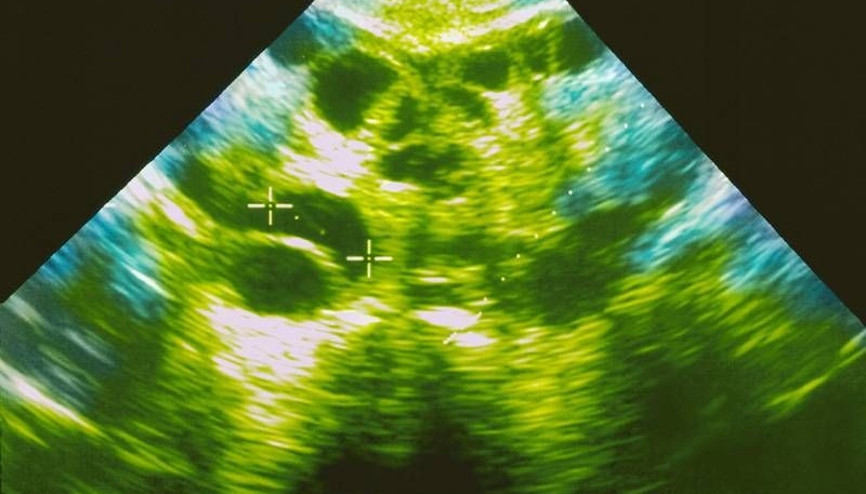

Polikistik Over, çoğunlukla 30 yaş üstü kadınlarda görülmektedir. Bu hastalık, hormonal dengeyi bozabilmektedir. Yumurtalıklarda bazı sıkıntılar oluşturan bu rahatsızlık, hipertansiyon, pıhtılaşma bozuklukları, obezite gibi sonuçları doğurabilmektedir. Erkeklik hormonunun baskın bir şekilde artış göstermesi üzerinde adet düzensizliği ve tüylenme ile sonuçlanmaktadır.

#Tekrarlayan Gebelik KaybıPolikistik over sendromu, insülin seviyesinin artmasına bağlı olarak meydana gelen hormonal düzensizlikler sonucu kısırlığa yol açabilen ciddi bir problemdir. Her 10 kadından birinde görülebilen Polikistik Over Sendromu düzensiz adet olma veya hiç adet olamama, yüzde veya vücutta tüylenme artışı gibi belirtiler gösterir. Bu problemi yaşayan kişilerin tedavisinde ilk adım fazla kilonun verilmesidir. Hastanın sağlıklı beslenme alışkanlığını kazanması ve düzenli egzersiz yapması önemlidir. Diyet ve egzersizle beraber ideal kilonun sağlanması yumurtlama fonksiyonlarının düzenlenmesini sağlayabilir. Yaşam tarzındaki değişiklik veya ilaç tedavilerine rağmen gebelik sağlanamayan hastalarda tüp bebek tedavisine ihtiyaç duyulabilir.

#Polikistik OverÇok sık rastlanan kadın hastalıklarından olan polikistik over sendromu nedenleri ve risklerinin yanı sıra tedavisi ile de araştırmalar arasında üst sıralarda yer alıyor. Peki, polikistik over sendromu nedir, nasıl tedavi edilir, riskleri nelerdir? Kadın Hastalıkları ve Doğum Uzmanı Op. Dr. İrem Yengel, kadınların büyük çoğunluğunu etkileyen polikistik over sendromu ile ilgili merak edilenleri hurriyet.com.tr okurları için anlatıyor...